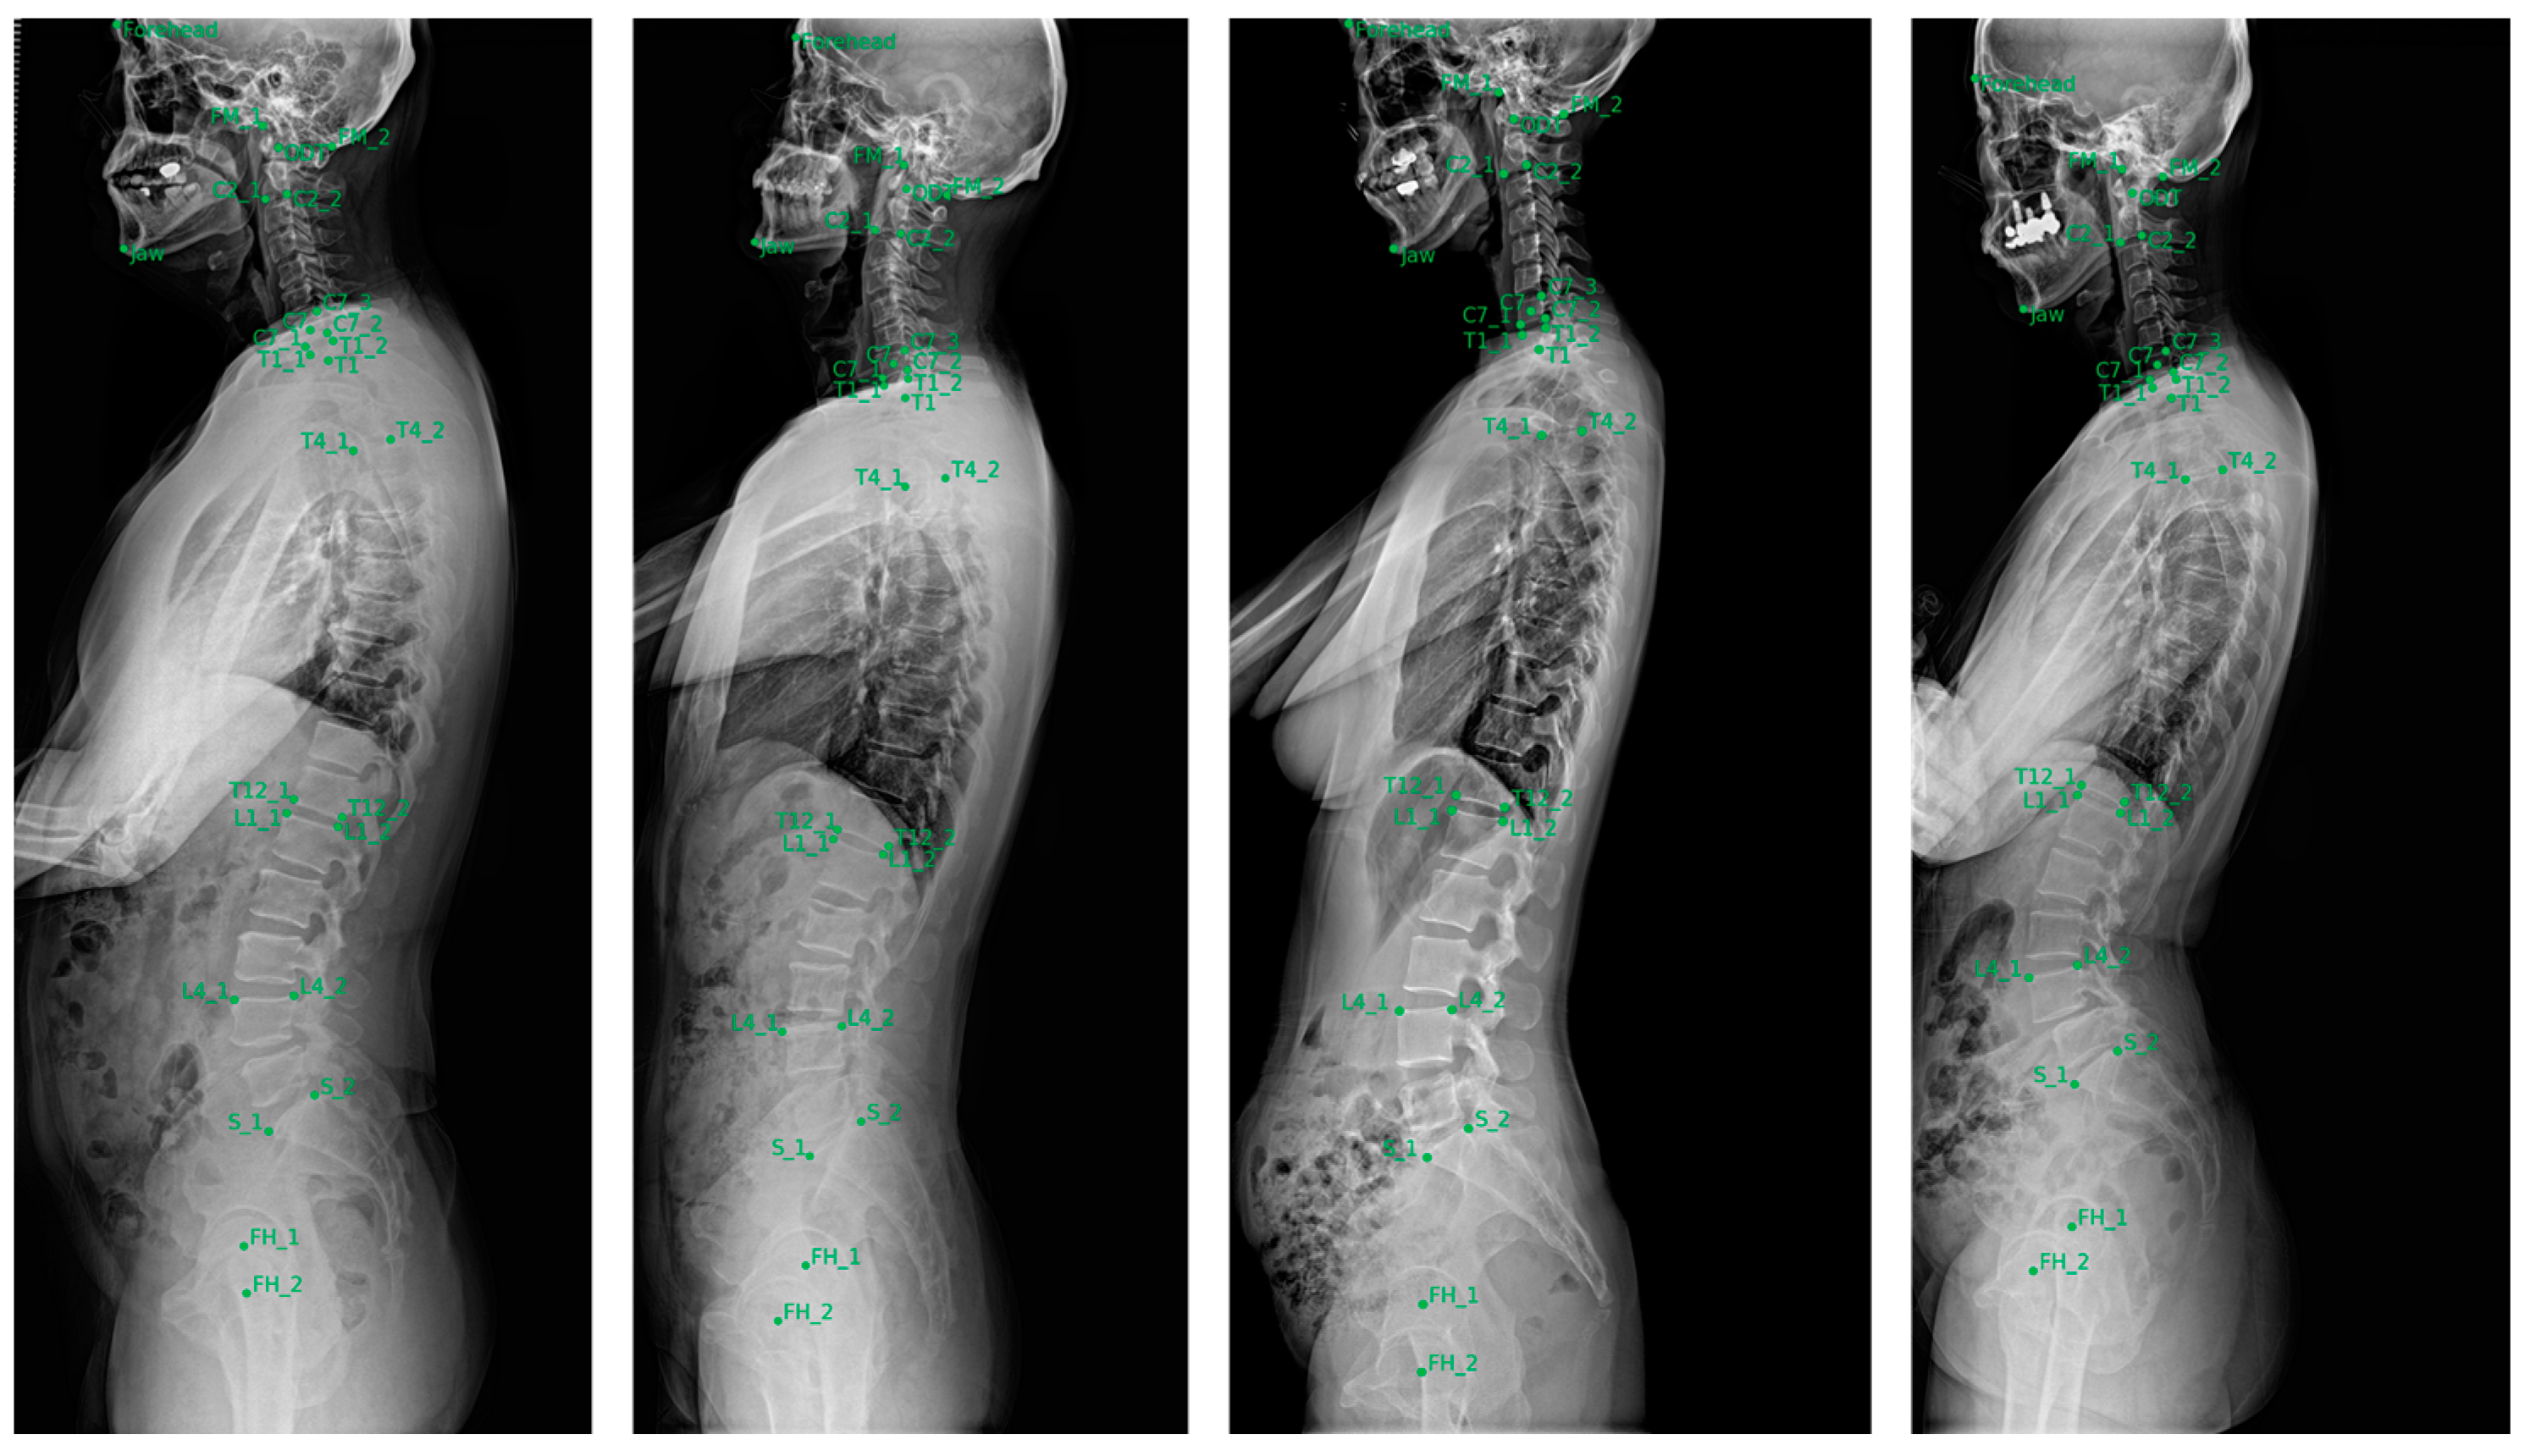

3.2. Performance of the Landmark Localizer

The landmark localizer showed the highest accuracy in identifying cervical landmarks, with a median error of 1.5–2.4 mm. This was followed by the lumbosacral landmarks, which exhibited a median error of 2.1–3.0 mm. In contrast, the thoracic landmarks displayed larger localization errors, with median values of 2.4–4.3 mm, indicating slightly reduced precision compared with the cervical and lumbosacral regions. Figure 5 shows a visualization of localized landmarks in the test set.

Figure 5.

Examples of landmarks automatically localized in the test set.